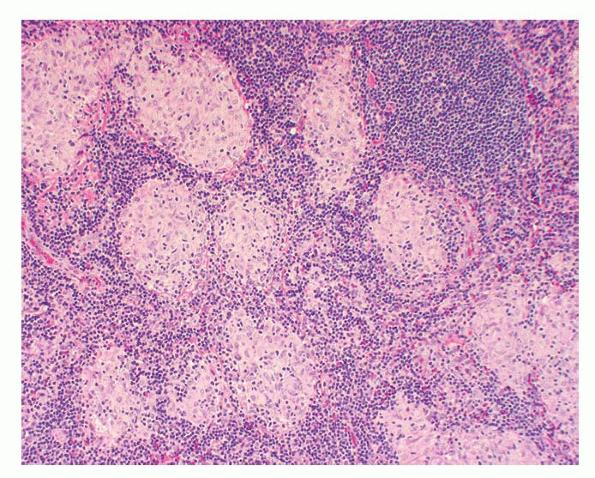

Like lesions in other organs, the cutaneous lesions of chronic, persistent sarcoidosis are characterized by the presence of circumscribed collections of epithelioid histiocytes-so-called epithelioid cell tubercles-which show little or no necrosis .

The papules, plaques, and lupus pernio-type lesions show variously sized aggregates of epithelioid cells scattered irregularly through the dermis with occasional extension into the subcutis (. In the erythrodermic form, the infiltrate shows small granulomas in the upper dermis intermingled with numerous lymphocytes

In typical cutaneous lesions of sarcoidosis, the well-demarcated islands of epithelioid cells contain few, if any, giant cells. Those that are present are usually of the Langhans type. A moderate number of giant cells can be found in old lesions. These giant cells may be large and irregular in shape. In a minority of cases, giant cells contain asteroid bodies or Schaumann bodies . Asteroid bodies , which are more common, are star-shaped eosinophilic structures that, when stained with phosphotungstic acid-hematoxylin, produce a center that is brown-red with radiating blue spikes . Schaumann bodies are round or oval, laminated, and calcified, especially at their periphery. They stain dark blue because of the presence of calcium. Neither of these two bodies is specific for sarcoidosis: They have been observed in a variety of other granulomas, including those of leprosy, tuberculosis, foreign-body reactions, and necrobiotic xanthogranuloma .

Classically, sarcoid has been associated with only a sparse lymphocytic infiltrate, particularly at the margins of the epithelioid cell granulomas . Because of the scarcity of lymphocytes, the granulomas have been referred to as “naked” tubercles. However, lymphocytic infiltrates in sarcoid may occasionally be dense, as in tuberculosis . Occasionally, small foci of fibrin or necrosis showing